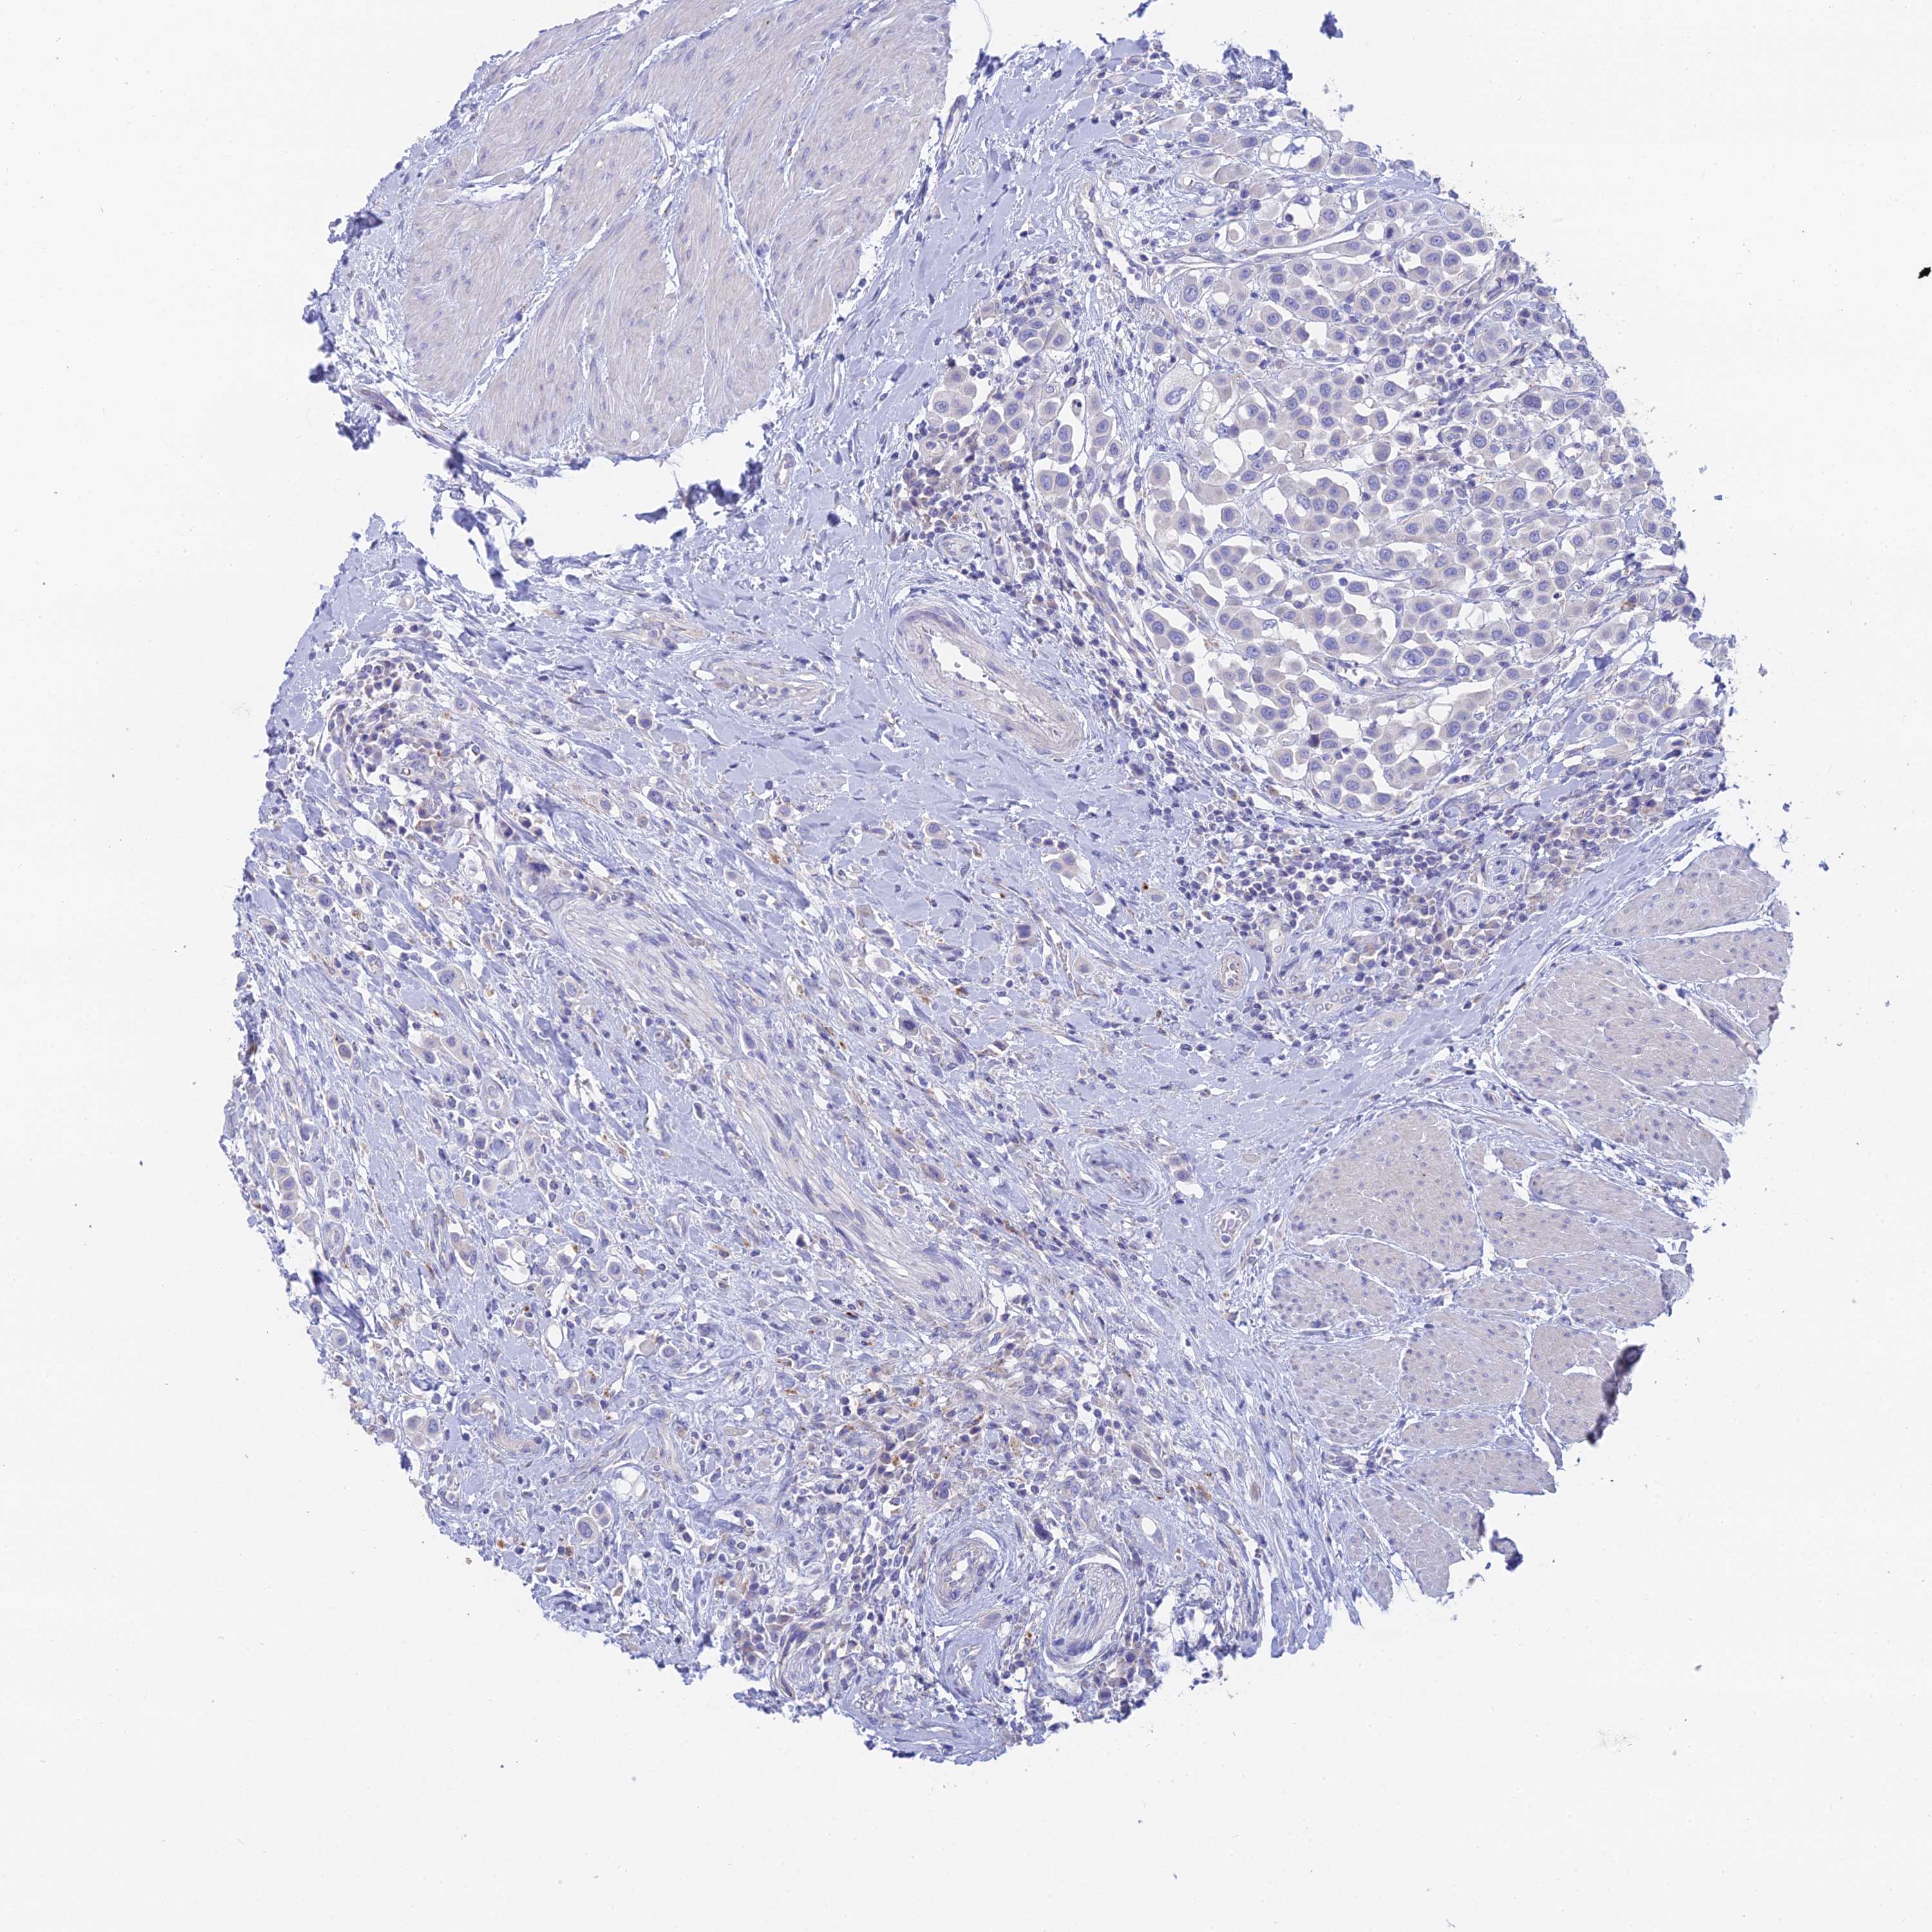

UROTHELIAL CANCER - Protein expressioni

A mouse-over function shows sample information and annotation data. Click on an image to view it in a full screen mode. Samples can be filtered based on level of antibody staining by selecting one or several of the following categories: high, medium, low and not detected. The assay and annotation is described here.

Note that samples used for immunohistochemistry by the Human Protein Atlas do not correspond to samples in the TCGA dataset.

Antibody stainingi

Antibody staining in the annotated cell types in the current human tissue is reported as not detected, low, medium, or high, based on conventional immunohistochemistry profiling in selected tissues. This score is based on the combination of the staining intensity and fraction of stained cells.

Each image is clickable and will lead to virtual microscopy that enables deeper exploration of all samples and also displays staining intensity scores, fraction scores and subcellular localization as well as patient and tissue information for each sample.

Antibody HPA042622

Staining

High

Medium

Low

Not detected

Intensity

Strong

Moderate

Weak

Negative

Quantity

>75%

75%-25%

<25%

None

Location

Urothelial carcinoma, High grade

Urothelial carcinoma, Low grade